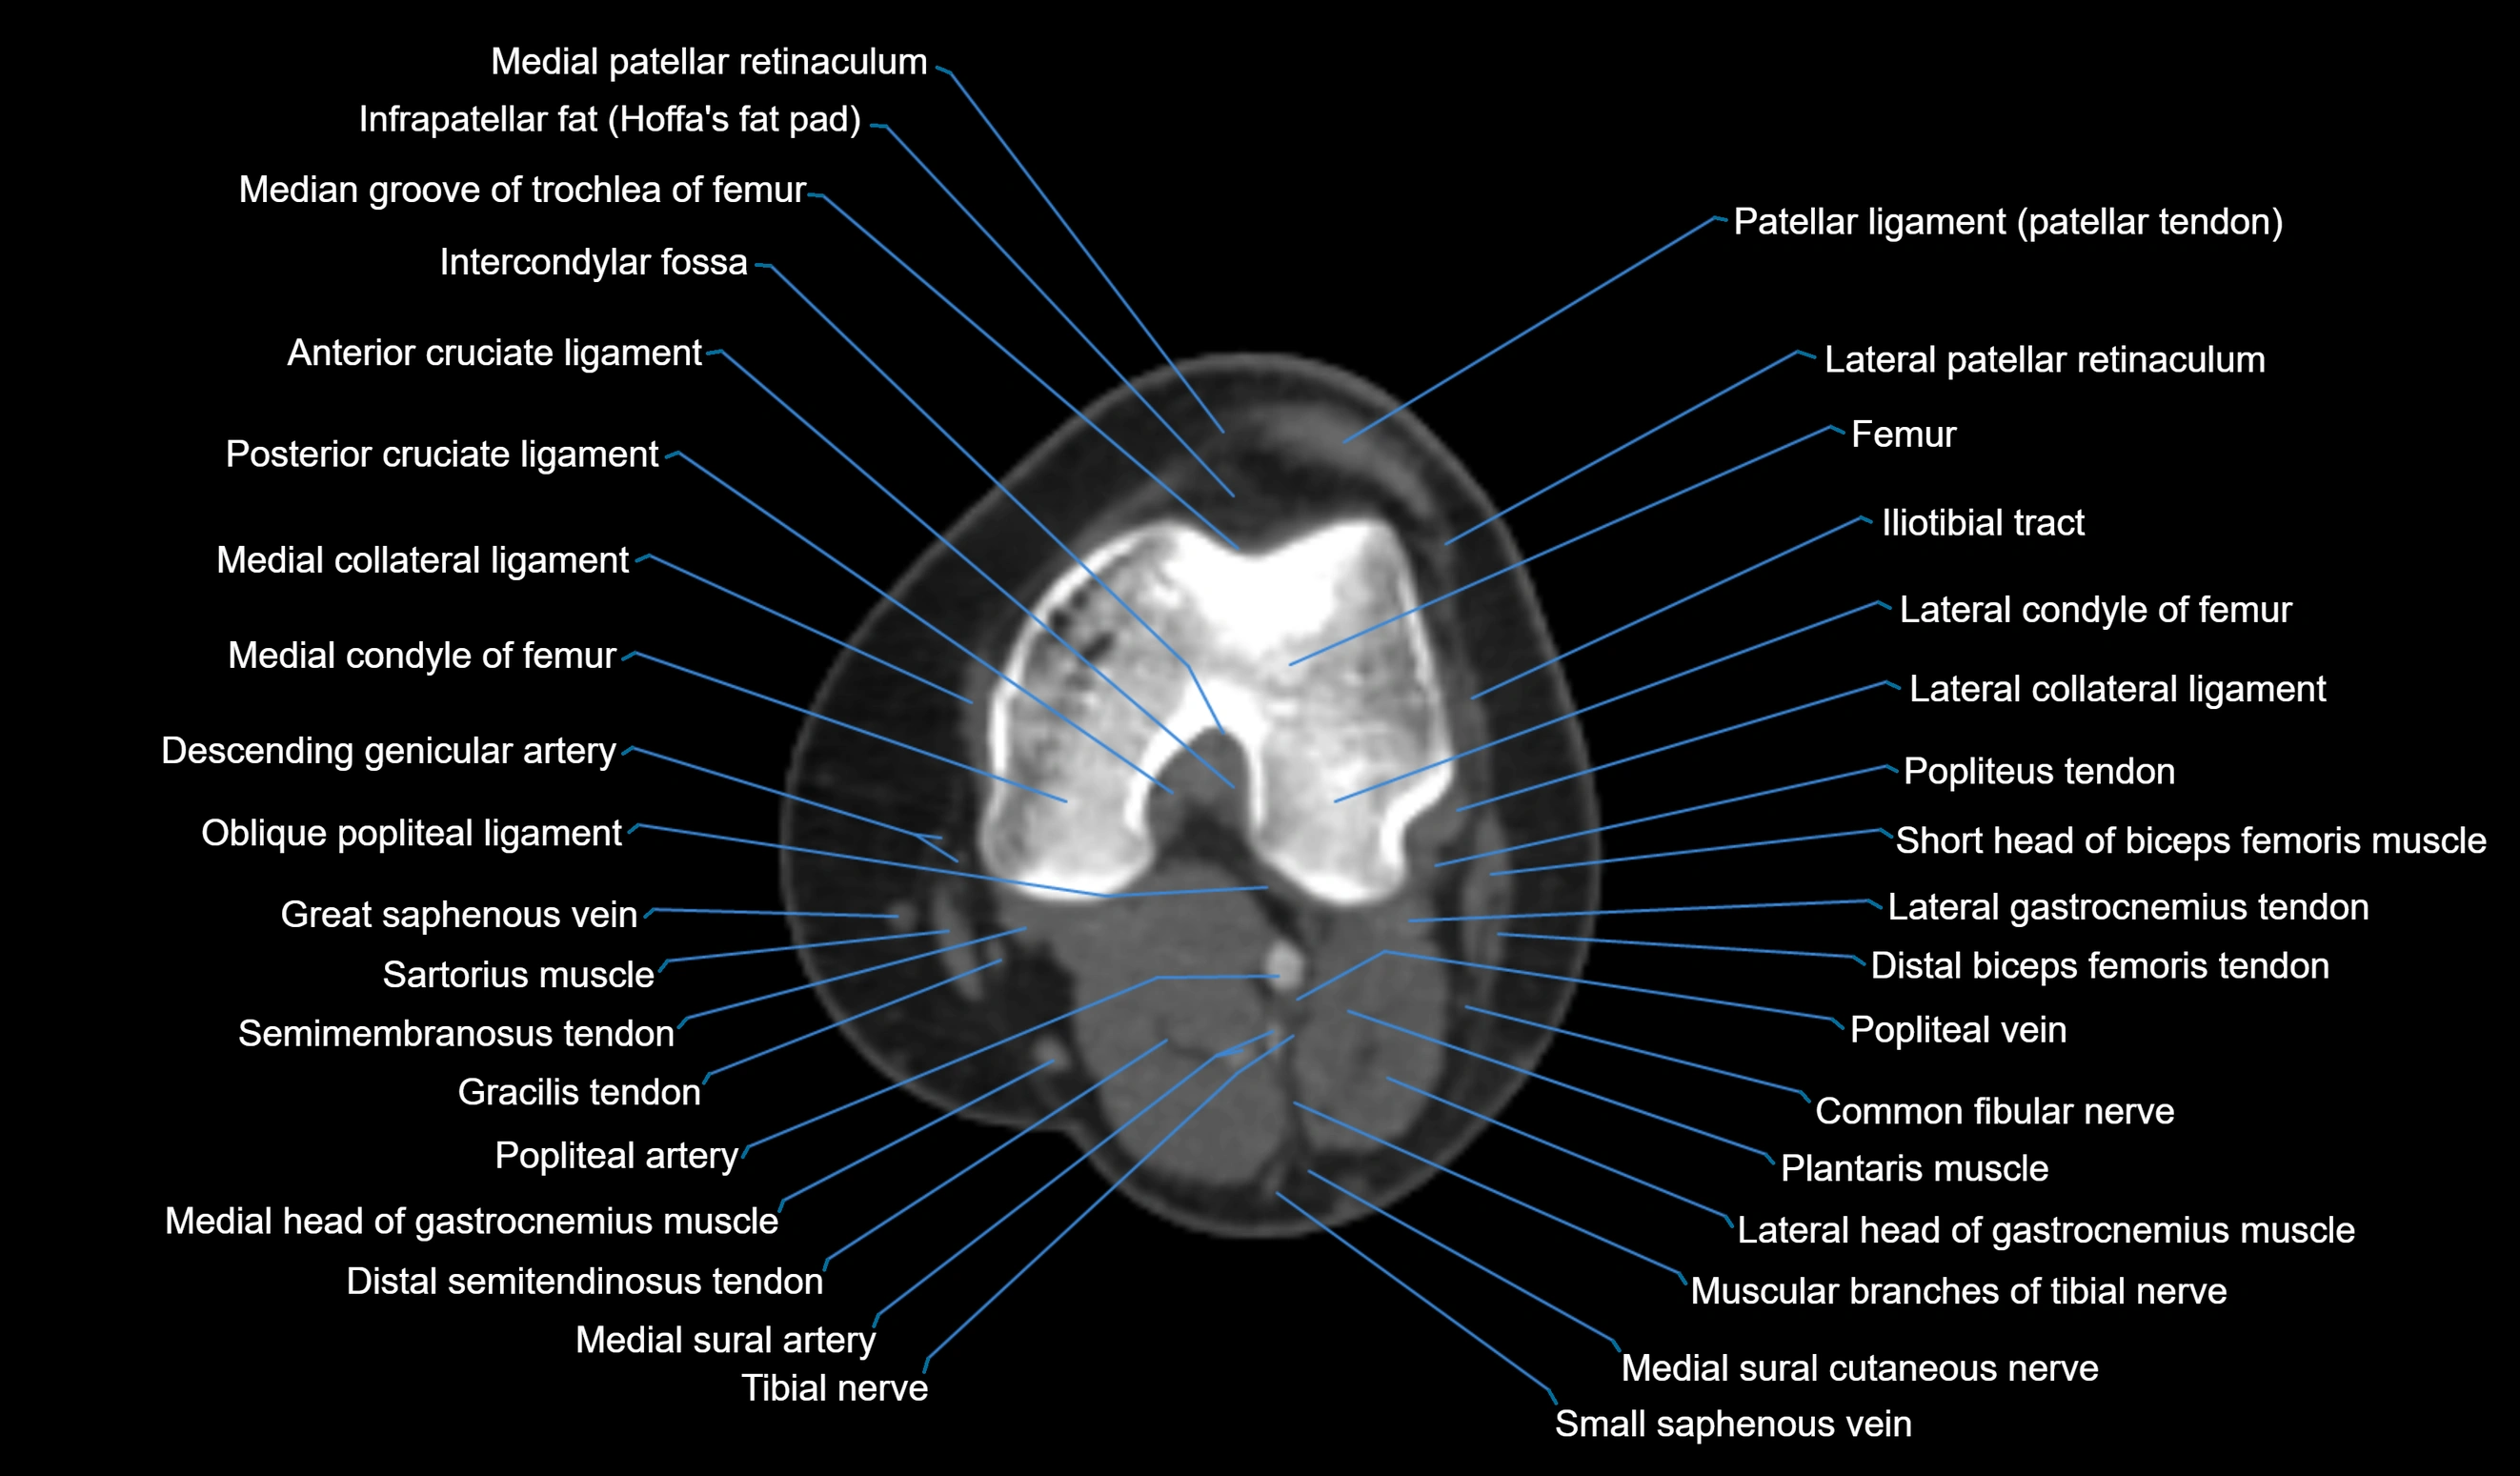

- Common fibular nerve

- Distal biceps femoris tendon

- Lateral collateral ligament

- Lateral condyle of femur

- Lateral gastrocnemius tendon

- Lateral head of gastrocnemius muscle

- Medial collateral ligament

- Medial condyle of femur

- Medial head of gastrocnemius muscle

- Medial sural cutaneous nerve

- Muscular branches of tibial nerve

- Oblique popliteal ligament

- Popliteal artery

- Popliteal vein

- Popliteus tendon

- Posterior cruciate ligament

- Sartorius muscle

- Semimembranosus muscle

- Small saphenous vein

- Tibial nerve